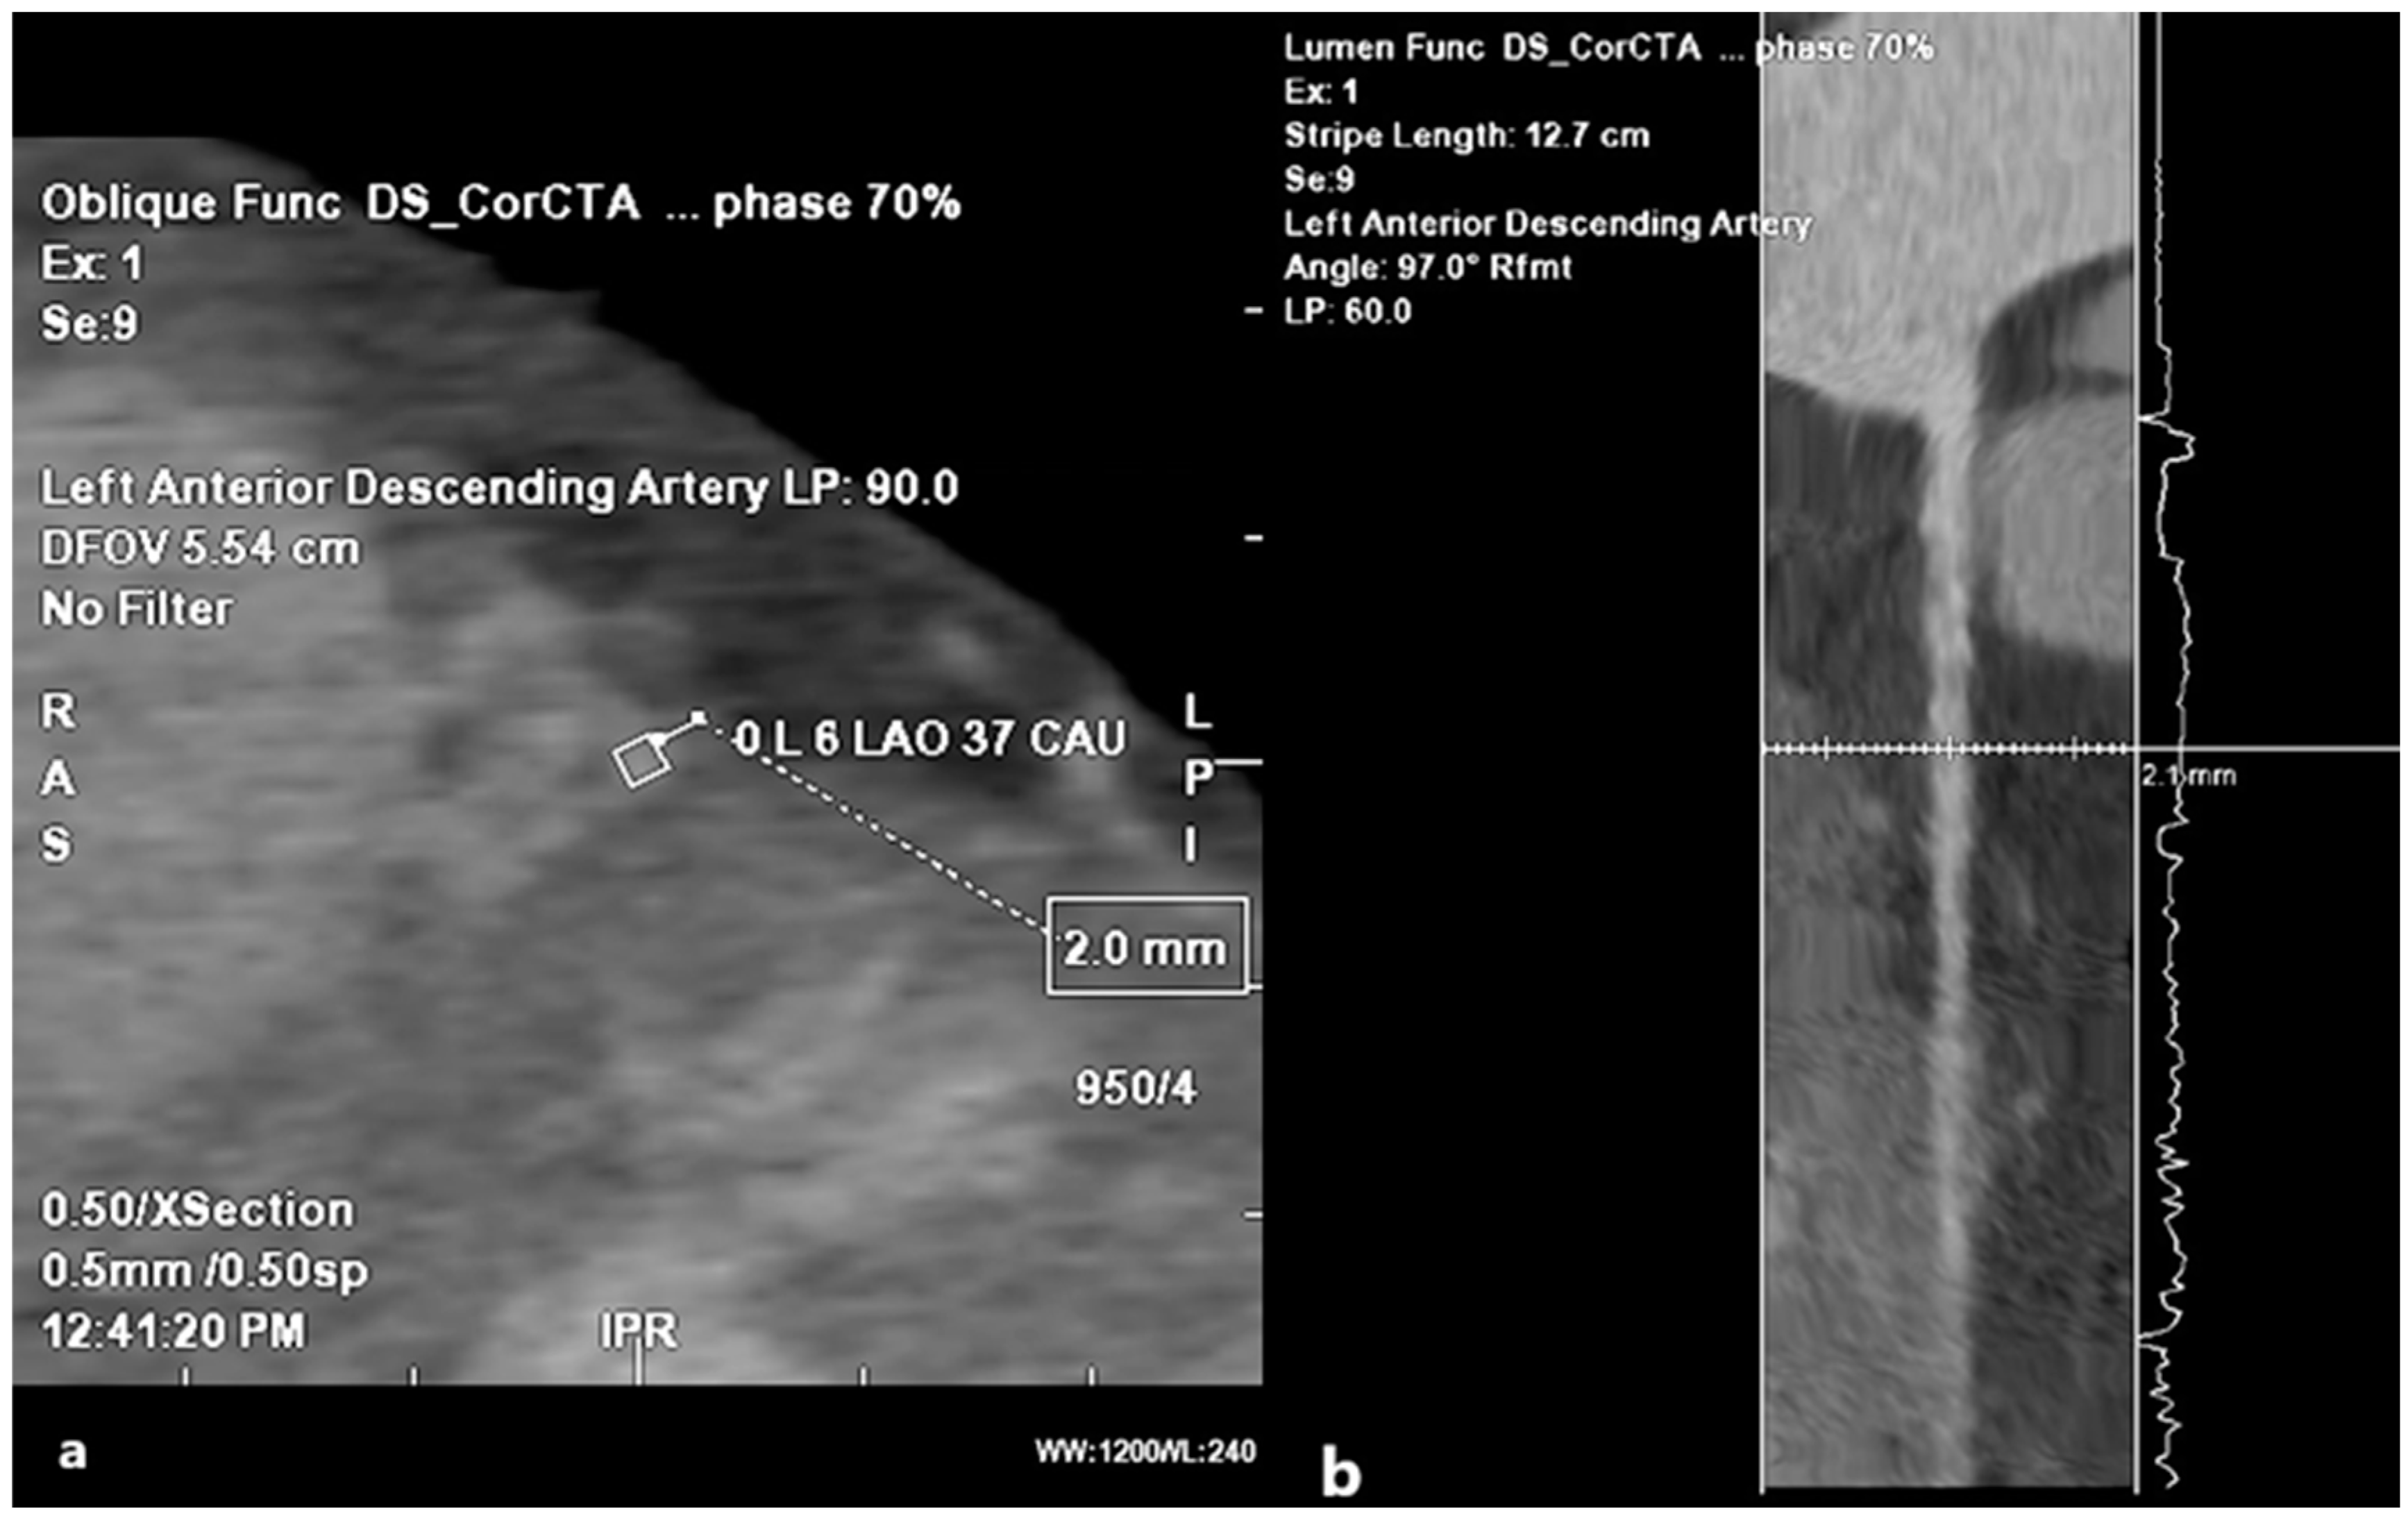

The coronary arteries have a typical epicardial path. Myocardial bridging (MB) represents the sinking of the coronary artery into the muscle, followed by resurfacing, and in most cases, is benign. Depending on the number of fibers that pass over the coronary artery, we distinguish between superficial MB (1–2 mm of the myocardium) and deep MB (>2 mm of the myocardium) bridges. This distinction is relevant because the depth is proportional to the compression exerted in systole; superficial bridges are typically asymptomatic [52]. We can talk about MB as a benign anomaly only if its depth does not exceed 2 mm (Figure 10); that is, if it is a superficial MB, not only the depth at which the coronary artery is located, but also the length of the segment that has intramural flow and the number of branches affected by the MB, will influence the onset of symptoms.

Figure 10. Myocardial bridging. (a) MDCT coronary angiography 2D planar view showing artery kinking into the myocardium (lumen labeled in rhomboid shape), at a depth of 2 mm. (b) Angiographic view of the myocardial bridging.